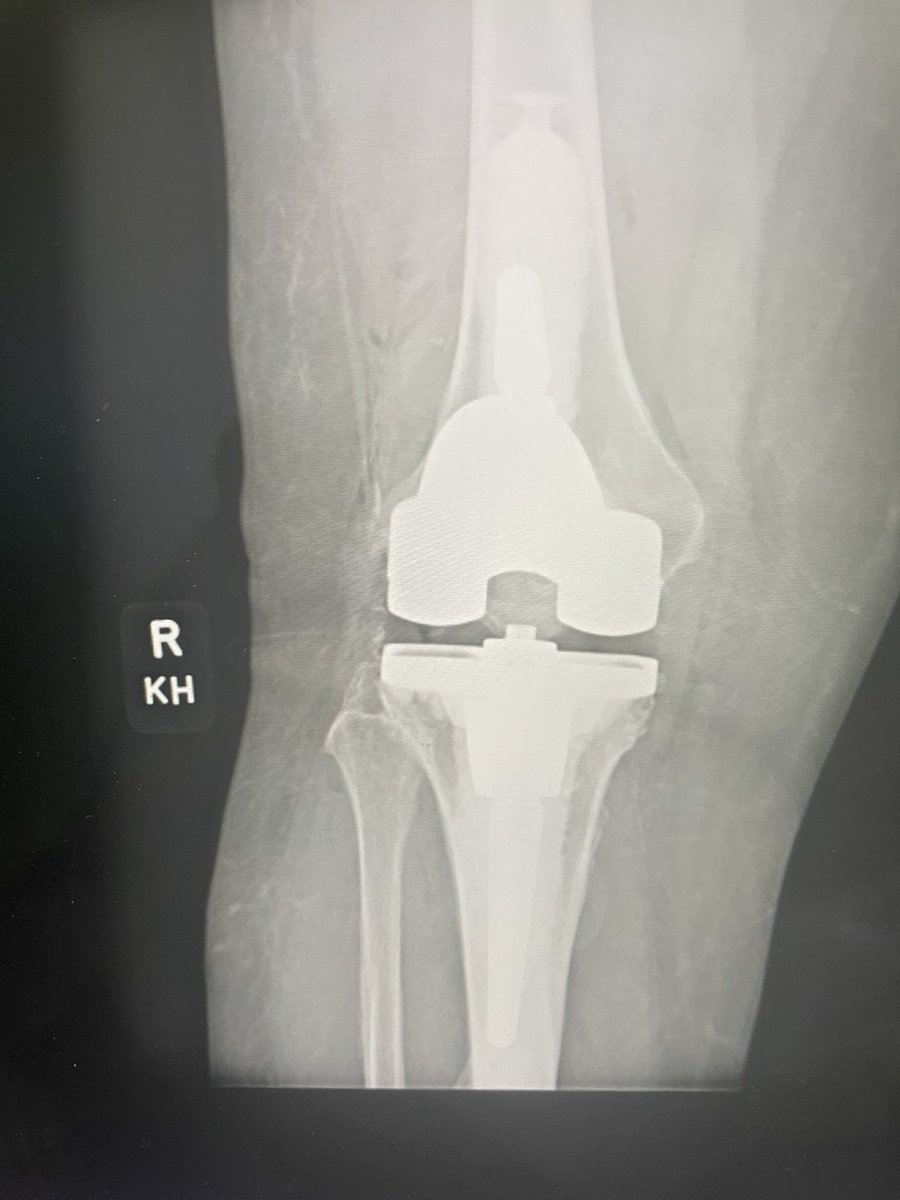

Implant ID? Is this the Zimmer one that has NOT been recalled? Currently asymptomatic